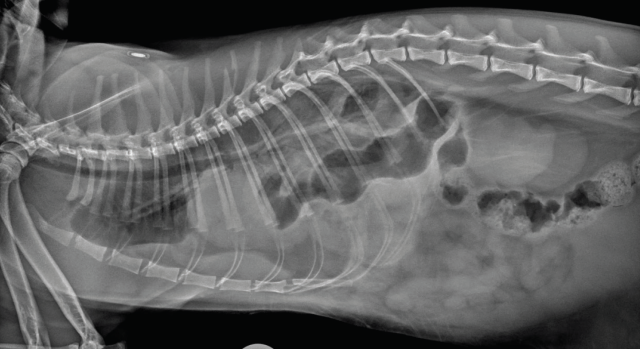

Many causes of dyspnoea are possible, and localisation is key in determining the required intervention. Thoracic trauma is common in these patients, even when there are no other visible injuries. Respiratory rate alone should not be used to exclude significant thoracic trauma and ideally survey radiographs should be performed in all patients (Figures 1 and 2) (Sigrist 2004). Table 1 gives some possible physical examination abnormalities with differentials and suggestions for diagnostics.

Pelvic trauma is a common finding in feline blunt-trauma patients and survey radiographs are recommended, even in ambulatory cats (Figure 9). Crepitus on manipulation of the pelvic limbs or palpation of fractures directly via rectal examination can provide an initial indication. Sacroiliac, coxofemoral and distal joint luxations, as well as long bone fractures are also fairly common and may be evident on physical examination or can be assessed on survey radiographs. The abdomen should also be carefully palpated for subtler abdominal wall ruptures (Figure 10).